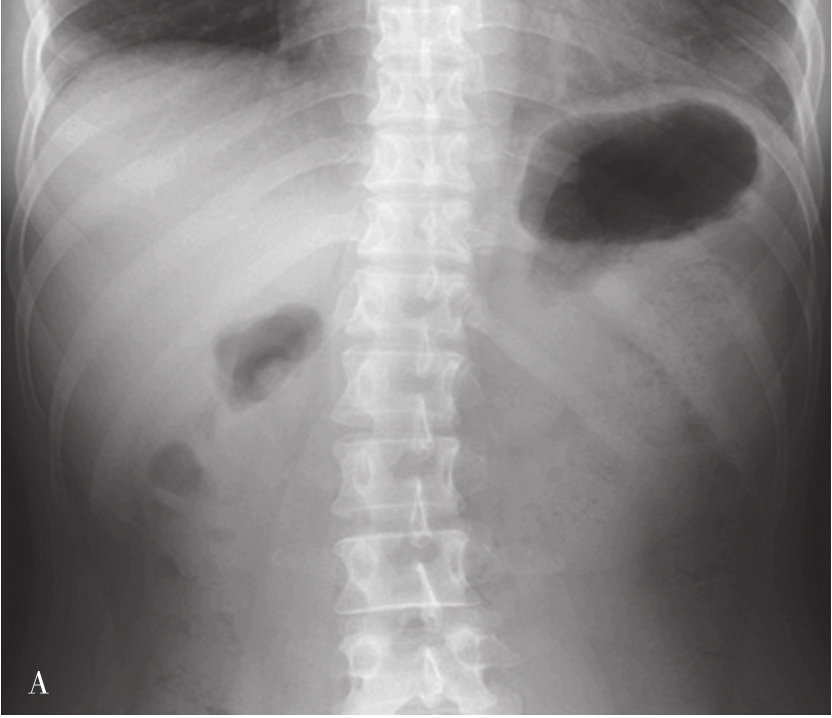

常规采取仰卧前后位(图5-21-33A),必要时取直立前后位和侧位。

上包膈顶,下至肝下缘盆腔。

X线平片对肝胆疾病诊断价值有限且阳性率低,目前其临床应用明显受限。平片可大概了解肝脏的大小、形态、位置、密度和胆道系统的阳性结石。肝脏增大多见于肝炎、肝硬化早期、肝脏肿瘤、肝脓肿、肝寄生虫、血液系统疾病和巴德-基亚里综合征(Budd-Chiari syndrome,BCS)等,可表现为膈顶的升高、结肠肝曲、脾区下移,胃受压移位等。肝区密度异常:肝区高密度影包括肝内钙化灶和胆道系统阳性结石;肝区低密度影主要为肝内胆管积气、部分为肝实质内及门脉系统内积气等。

目的在于进一步了解肿大肝脏对胃、十二指肠和结肠肝曲的压迫和移位情况。肝癌患者常伴发肝硬化,应行钡餐检查除外食管、胃底静脉曲张,以及阻塞性黄疸与胃肠道的关系等。

检查前准备:行胃肠道钡餐患者常规均应检查前禁食和禁水6h以上,检查前3天不服用含铁、铋、钙等不透X线元素的药物,以免残留在肠道内影响观察。常规采用钡剂检查(图5-21-33B、图5-21-33C),如有新鲜消化道出血患者禁行钡剂检查,必要时可行泛影葡胺等碘水检查。

图5-21-33 胃肠道钡剂检查图片

A.正常上腹部仰卧前后位,可见胃及肠管内少量积气;B.正常食管充盈像;C.正常站立位胃充盈像。